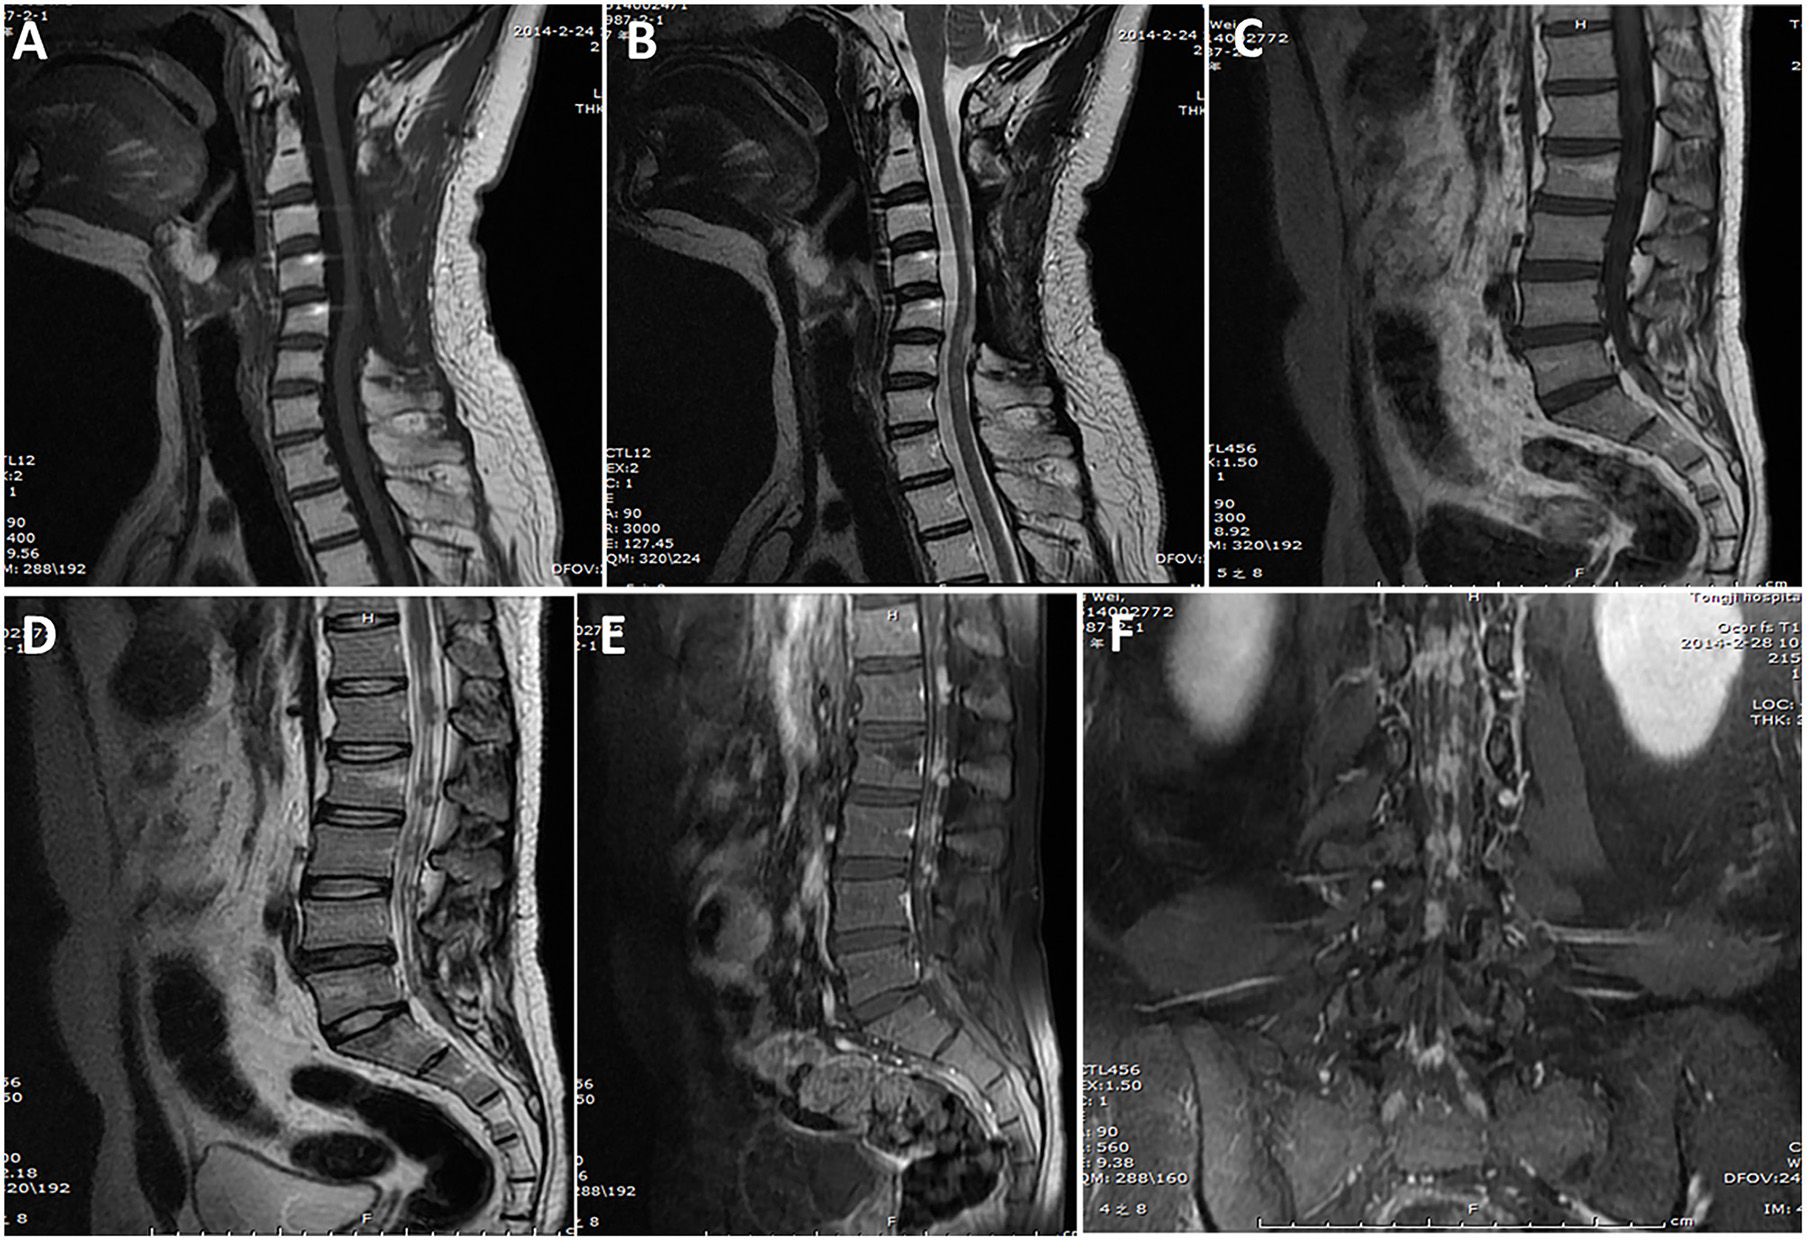

Radiological data are summarized in Table 1. Based on MRI scans, the lesions were hypointense (n = 35, 87.5%) or isointense (n = 5, 12.5%) on the T1-weighted images (Figures 1–3), and isointense (n = 8, 20.0%) (Figures 1, 2) or hyperintense (n = 32, 80.0%) on the T2-weighted images. Thirty-five (87.5%) lesions showed significant heterogeneous enhancement (Figures 1–3) and five (12.5%) lesions showed significant homogeneous enhancement on MRI scans. The lesions involved the cervical spine in six (15.0%) cases, thoracic spine in 24 (60.0%) cases, lumber spine in 13 (32.5%) cases, and sacrum in five (12.5%) cases, respectively. Among these cases, one case showed involvement of both the cervical and thoracic spines, three cases showed involvement of both the sacral and lumbar spines, and four cases showed involvement of both the thoracic and lumbar spines. In addition, tumor lesions involved a single segment in seven (17.5%) cases, and multiple segments in 33 (82.5%) cases. Seventeen patients were radiographed for intraspinal tumors and vertebral bone destruction (Figures 1, 2). Regarding the subtypes, the spinal canal type (Figure 1) was detected in 32 (80.0%) cases and vertebral type (Figure 2) was detected in eight (20.0%) cases.

Figure 3. A case of primary intradural ES/pPNET at the C3–C5 level. Images obtained 14 months after the first surgery (A,B) showed no tumor local recurrence at the C3–5 level (lack of preoperative MRI examination findings), but they did show multiple metastases in the spinal canal through the cerebrospinal fluid (C–F).

The mean follow-up period was 23.8 (range, 2–93) months. At the last follow-up, local recurrence occurred in 24 (60%) cases, and seven patients underwent a second operation and one patient underwent a third operation. Distant metastasis occurred in 11 (27.5%) cases. The distant metastatic sites was the lung in six cases, rib in one case, sternum in one case, mediastinum in one case, and spinal cord in two cases (Figure 3).